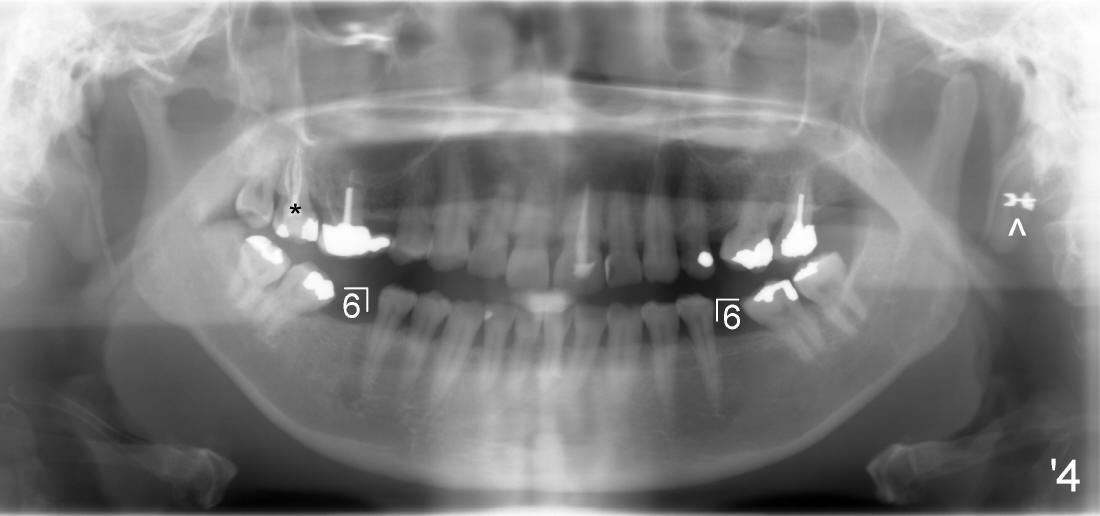

其实本文题目是如何让植牙病人找上门。冯女士四十二岁,四五年前因左下六牙痛第一次登门就诊,X光片显示牙根很长(图一),近中根根尖有阴影(>),那根牙根弯曲,总之,稀里糊涂开始根管治疗,结果有四根根管(图二),又长又弯,远中舌侧根断针(>),但是重新通过,辛辛苦苦完成根管治疗时才发现远中舌侧根弯弯曲曲(图三箭头,黑色箭头指向原来断针)。这些年来这颗牙齿没问题,但是左上七号牙老是发炎,全景片表明那颗牙齿根分叉处有阴影(图四箭头),一直劝她拔牙,植牙,上个月她终于同意拔牙,准备年底植牙。只有认认真真为病人解决痛苦,才能赢得他们信任,一旦他们需要进一步治疗,也会乐意开口。根管治疗做起来吃力,但是最能显示赤胆忠心。做好根管治疗是开展植牙第一步,愿意保留牙齿的人,视牙如金,如果我们尽力而保留不了,他们还是愿意更上一层楼;轻易拔牙的病人很少后来回来做植牙。

五十一岁Junita牙齿不好,右上有一个悬臂桥(图一’:5.6),她要找一位医生能解决她所有的牙科问题:右上7牙髓炎(图一’),右下,左下6植牙(图’四)。她最大问题是害怕牙科治疗,根管治疗中不太配合:牙胶尖插入后拍摄X光片,位置不对,没有显示根尖(图二’),最后根管充填效果尚可(图三’),疼痛没有了,病人的心被我们收买了,接着我们准备分期给右下,左下6植牙,但是她坚决反对,要求一次完成两个植牙,因为她非常怕痛,对钻耳环洞都害怕极了,做了一个耳环(图’四:箭头),再没有勇气回去做第二个。好了,明天做二个植牙,到时向大家汇报。这位胆小病人上战场时胆怯了,迟到一会儿,说她不愿意左右各做一个植牙,影响吃饭。由于右下近远中间隙比左下大些,我们先做右下植牙,回学术讨论园地